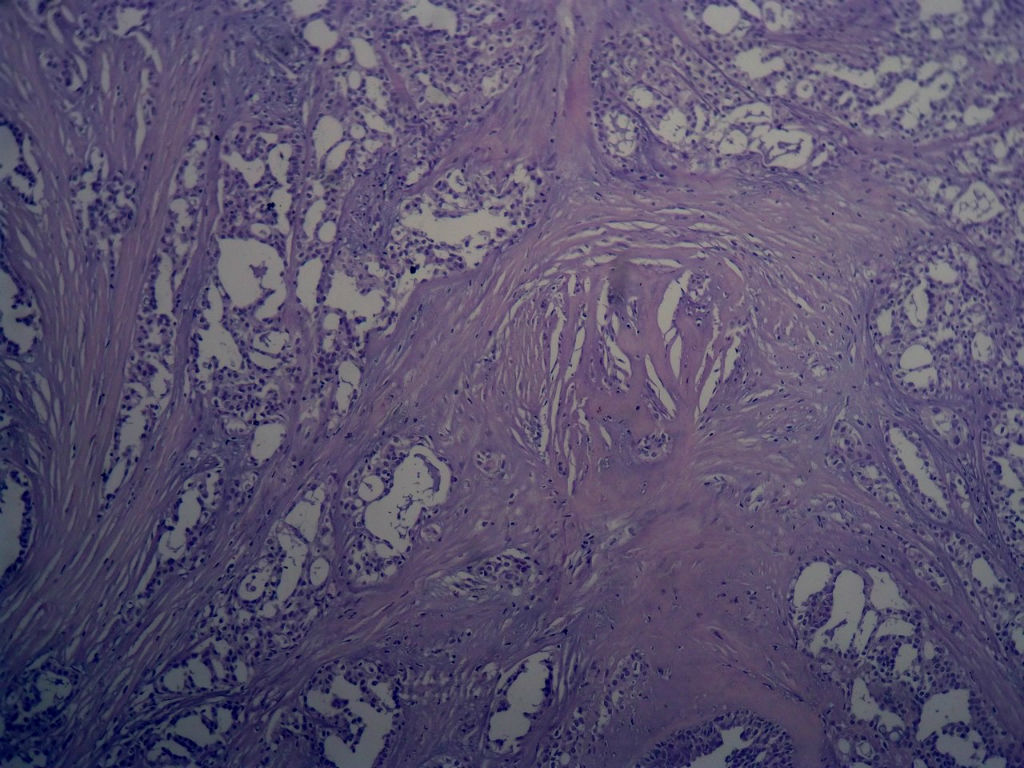

本例太完美了,也非常惊险,真的,至少在我们中国的这个病理环境下能做到这样真心不错。这是个罕见病例,居然冰冻让你碰上了,从冰冻——常规——IHC都完备。我从冰冻看到常规未看免疫组化之前还一直犹豫是不是癌?是癌但一定是您说的分泌性癌吗?看常规时只是觉得浸润性癌够了,后来看到常规的筛状结构+分泌物才确定形态学也够了,就差IHC了,结果您贴出来上级医院的IHC结果真的是3阴,S-100+,高分子量CK部分+,这个表达模式完全符合分泌性癌(我也遇到一个分泌性癌,IHC表达方式完全和您的这例一样),当然必须是结合形态学了。

这个癌既符合3阴乳腺癌,又符合基因上分类的基底细胞样乳腺癌,只不过预后很好,和一般意义上的3阴乳腺癌、基底细胞样乳腺癌不一样!如果有条件再做下FISH检测到ETV6重排那就更完美了

Secretory breast carcinomas (o0.15% of breast tumors) are associated with a characteristic morphology and a

favorable prognosis. Remarkably, this entity is the only epithelial tumor of the breast with a balanced

translocation, t(12;15), that creates an ETV6-NTRK3 gene fusion encoding chimeric tyrosine kinase also

encountered in cellular mesoblastic nephroma and infantile fibrosarcoma. The aim of this study was to

determine the phenotypic class (ie luminal A/B, ERBB2, basal-like) of secretory breast carcinoma. A series of six

secretory breast carcinomas were identified in our files. The ETV6 rearrangement was confirmed in all cases by

fluorescence in situ hybridization. Immunophenotype was assessed with anti-ER, PR, ERBB2, KIT, EGFR,

E-cadherin, vimentin, PS100, smooth muscle actin, basal (CK5/6 and 14), luminal cytokeratins (CK8/18) and p63

antibodies. In situ and invasive components shared the same immunoprofile and were ER, PR, ERBB2 negative

with expression of basal cytokeratins. ETV6 gene alterations were present in both in situ and invasive

components, highlighting their genetic similarities. The immunoprofile data (triple-negative with expression of

basal markers) showed that secretory breast carcinomas with ETV6-NTRK3 fusion gene belong to the

phenotypic basal-like spectrum of breast carcinomas. These results support the hypothesis that secretory

breast carcinomas have immunohistochemical and genetic features that distinguish them from other basal-like

tumors of the breast.